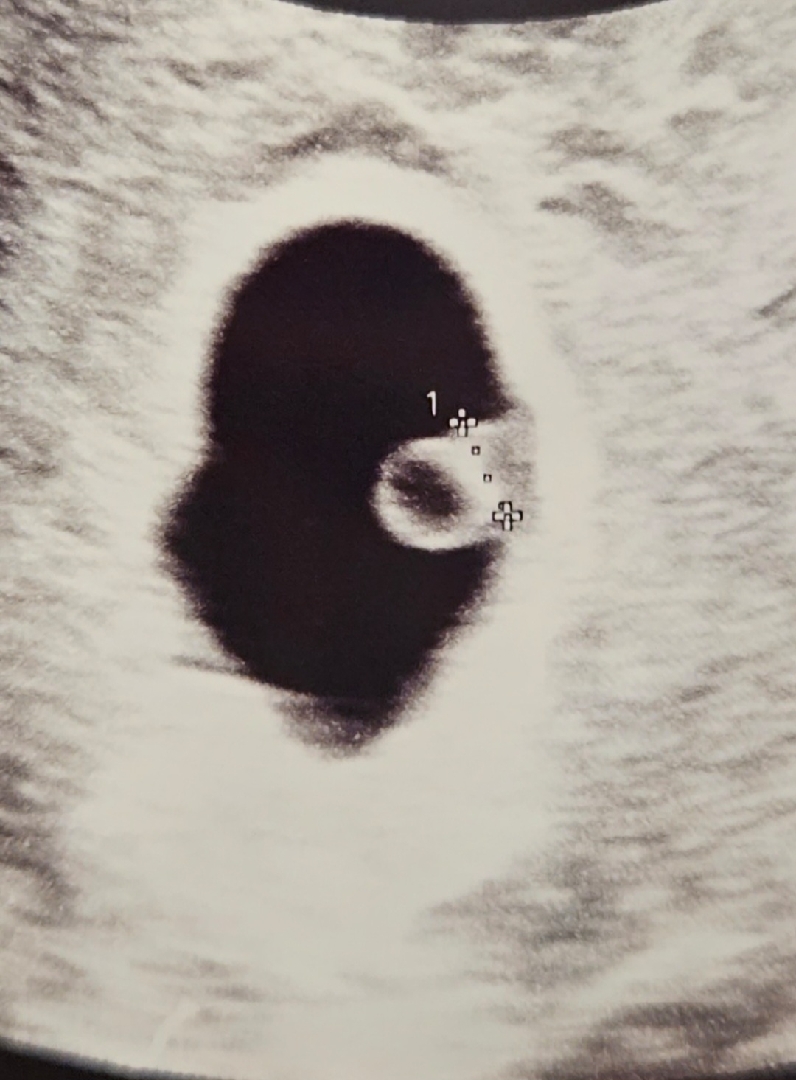

우리띠용이 잘크고 있대요!!

몇일전에 또 피비침과 복통이있어서 걱정하고 병원갔는데 잘 크고 있다네요!!!!ㅎㅎ 아기집도 지난주보다 엄청 커졌답니다 난황옆이 애기라는데 어떻게 크는건지 신기합니다'-' 담주에 심소 들으러가요!